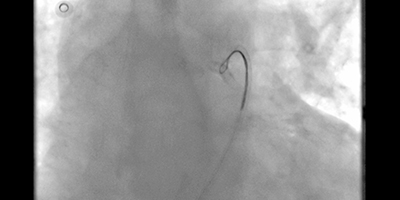

Card image cap

Coronary Sinus Stenting to Enable Left Ventricular Lead Implantation During Cardiac Resynchronization Therapy: A Case Report

See Videos